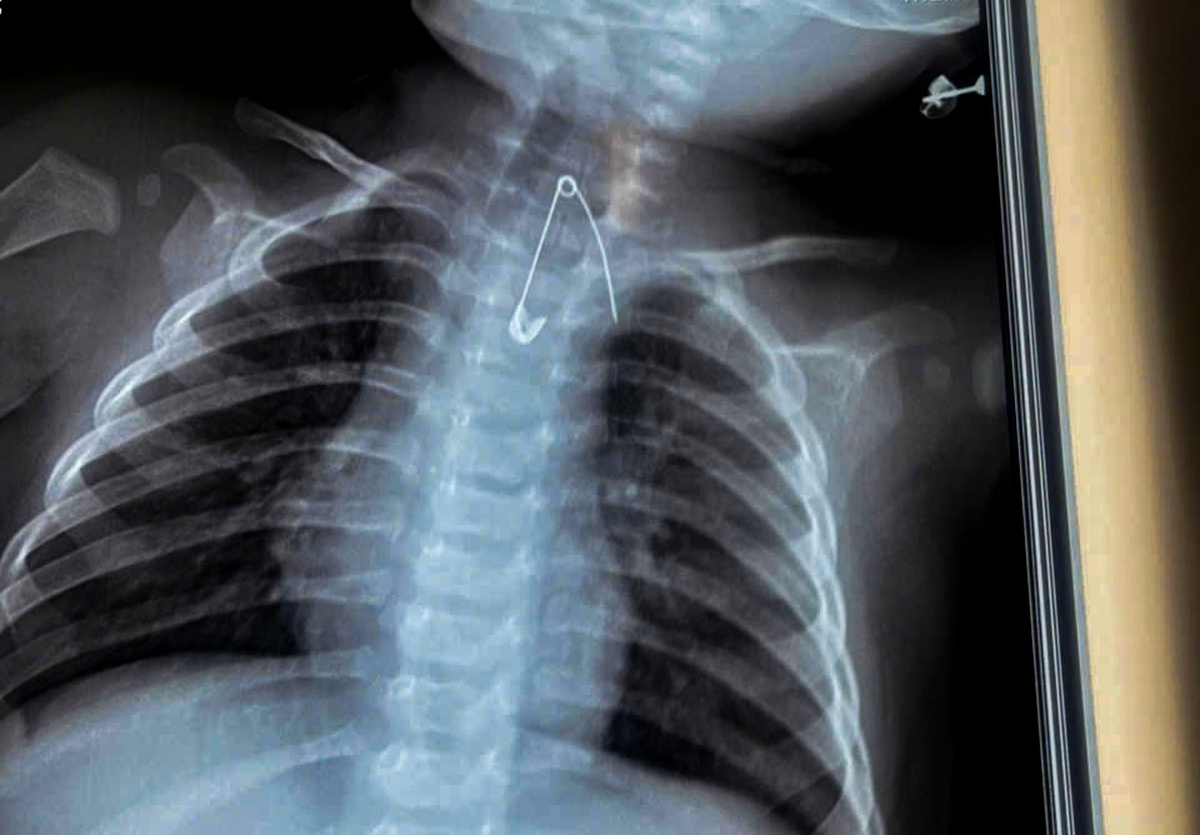

Cứu sống hai em bé nuốt kim băng và cây kẹo mút

Ngày 8-1, Bệnh viện Sản Nhi Cà Mau cho biết các bác sĩ vừa tiếp nhận và xử trí thành công hai trường hợp bệnh nhi nuốt dị vật đặc biệt nguy hiểm, trong đó có ca thủng tá tràng và ca dị vật sắc nhọn nằm sát động mạch chủ, đe dọa đến tính mạng.